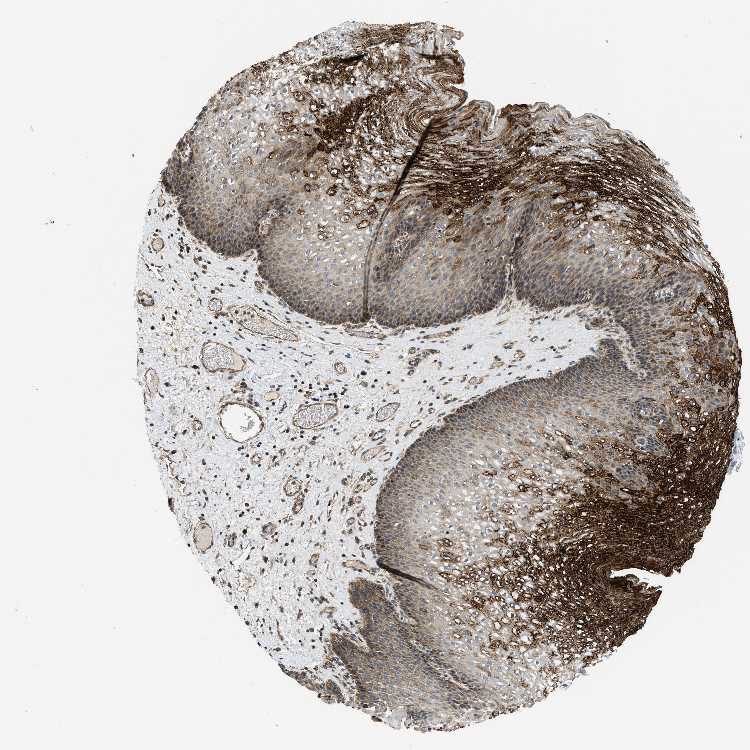

ESOPHAGUS - Antibody stainingi

Antibody staining in the annotated cell types in the current human tissue is reported as not detected, low, medium, or high, based on conventional immunohistochemistry profiling in selected tissues. This score is based on the combination of the staining intensity and fraction of stained cells.

Each image is clickable and will lead to virtual microscopy that enables deeper exploration of all samples and also displays staining intensity scores, fraction scores and subcellular localization as well as patient and tissue information for each sample.

Antibody HPA003539Antibody CAB018374

Squamous epithelial cells LowHigh